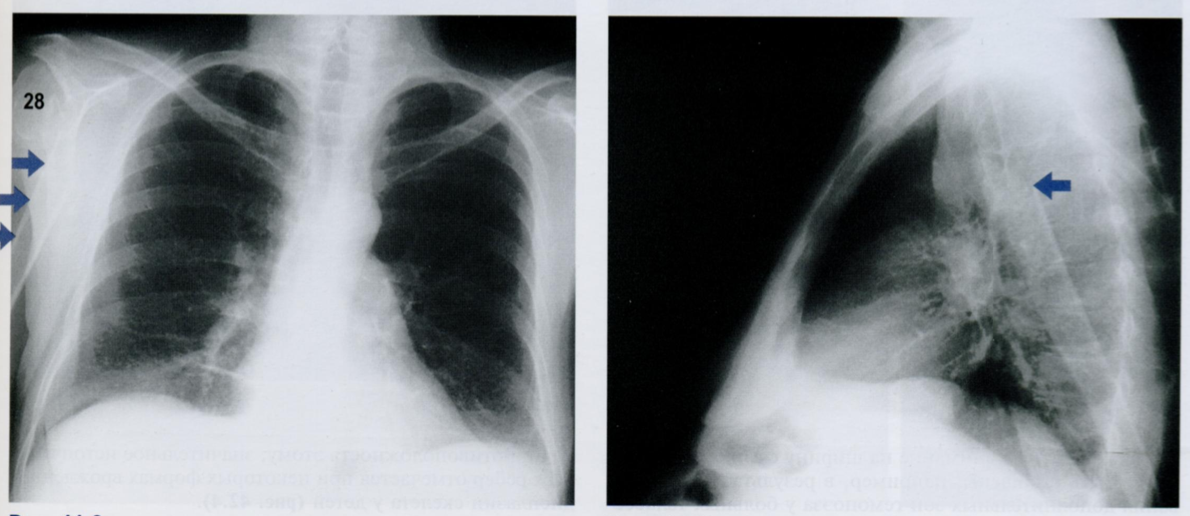

Как Вы оцените объекты отмеченные на снимке, принимая во внимание, что клиника и снимок никак нет коррелируют?

ЗПП - задняя прямая проекция и БП - боковая проекция

То есть, вероятнее всего, это артефакты. Какие?

Стрелками на первом снимке отмечены заплетенные и распущенные волосы, которые приводят к появлению артефатков, которые имитируют восходящий пневмомедиастинум или подкожную эмфизему.

На втором снимке мы видим ампутационную культю руки в БП, которая выглядит как веслообразное затемнение на уровне проекции верхнего средостения. Может имитировать новообразование.